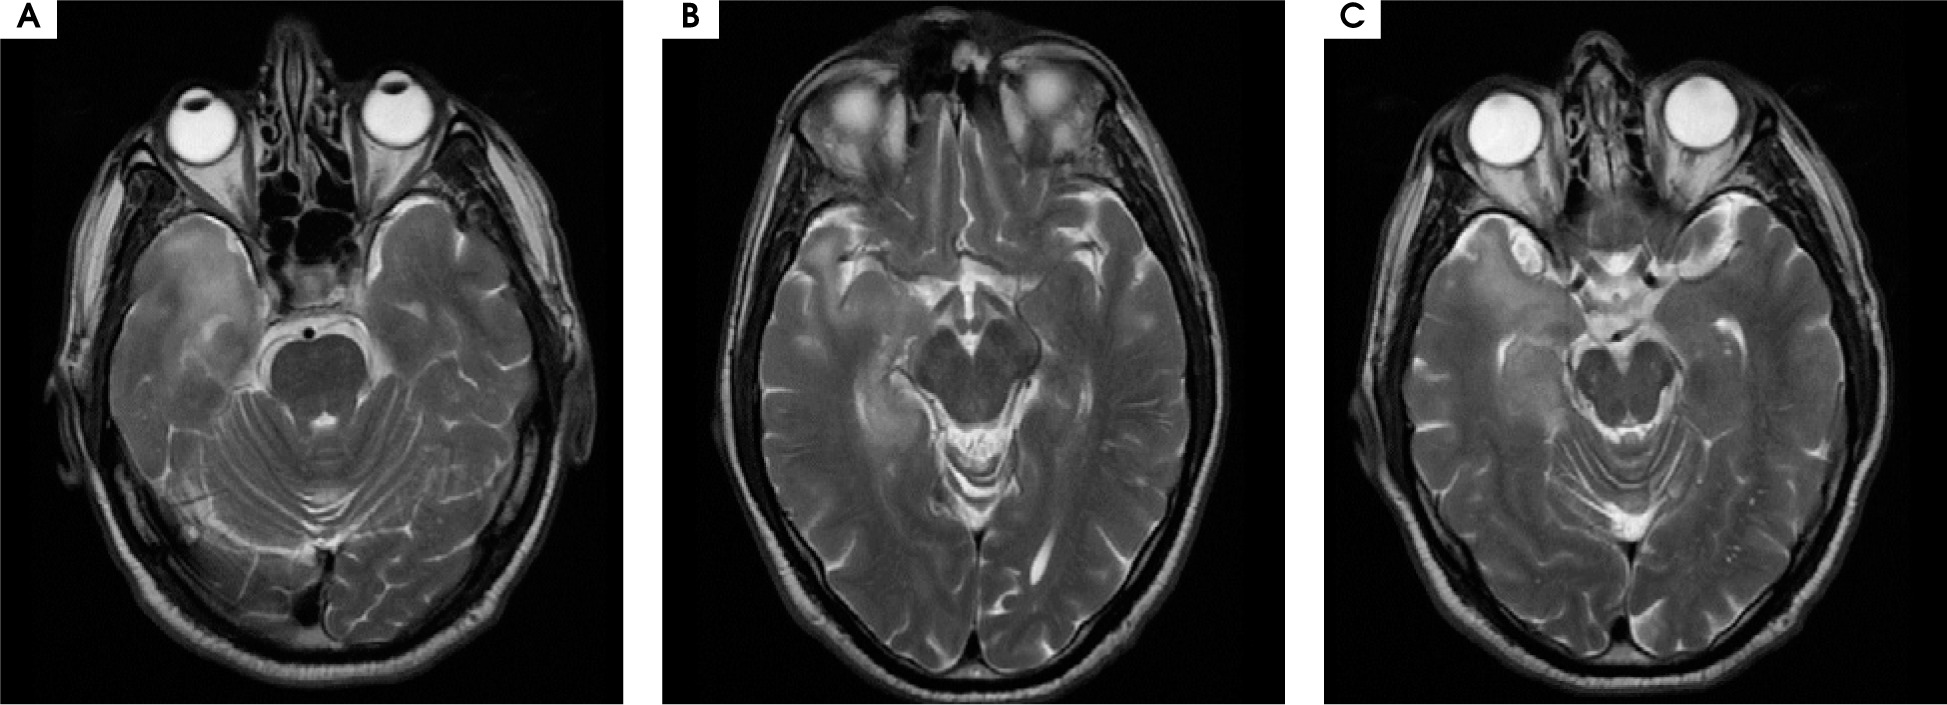

A 48-year-old male patient was admitted to the outpatient neurological clinic with complaints of numbness on the left side of his face, instability, spasms in all four extremities lasting for about 45 seconds, insomnia, and excessive talkativeness. In neurological examination, his general condition was good, he was conscious but showed psychomotor agitation, with difficulty concentrating and excessive talkativeness. He had dysarthria; his muscle strength and gait were normal. Sensory examination was normal, cerebellar examination was normal. Deep tendon reflexes (DTR) were normoactive in both upper and lower extremities, plantar response was flexor. There was no sign of meningeal irritation. In brain magnetic resonance imaging (MRI), an iso-hyperintense appearance was recorded in the hippocampus trace in the medial part of the right temporal lobe, and in the hyperintense ADC map in DWI. At this level, hyperintense cortical-subcortical and periventricular signal changes are accompanied on T2 images. Faint sulcal-like enhancements were observed. MRI findings were evaluated in favor of encephalitis (Figure I).

Figure I

Hyperintense signal changes in the right temporal lobe hippocampal region on brain MRI T2 sequence

Anti-NMDA receptor encephalitis is a type of autoimmune encephalitis caused by the development of IgG type antibodies against NMDA glutamate receptors. It was first identified in 2007 [1, 2]. The majority of patients are young females with ovarian teratoma, which is mostly associated with malignancy. In some studies found in the literature, it has been shown that the production of anti-NMDA receptor antibodies increases during the course of Herpes simplex encephalitis (HSE) and encephalitis occurs clinically. Psychiatric symptoms may occur. Imaging reveals findings only in 33% of cases [1, 2, 5, 6]. Showing hyperintensity in the hippocampus, cerebral-cerebellar cortex, frontobasal and insular areas, and brainstem elements in T2W and FLAIR sequences with mild meningeal enhancement. However, the only MRI finding with prognostic value is cerebellar atrophy which is an indicator of poor prognosis. Patients may show antibodies in the first cerebrospinal fluid study, or antibodies may be positive in recurrent CSF and serum studies [1, 2, 7-9]. EEG changes may be detected but the only EEG pattern specific to the disease is a superimposed fast activity in generalized rhythmic delta activity and which is called “extreme delta brush” [1, 3, 10, 11]. Corticosteroids, intravenous immunoglobulin (IVIG), plasmapheresis, cyclophosphamide and rituximab can be applied in the treatment of the disease. When malignancy is detected, an appropriate treatment for malignancy should be planned. The recovery rate is high when treatment is given, but untreated conditions can be fatal [2, 5, 6, 12].